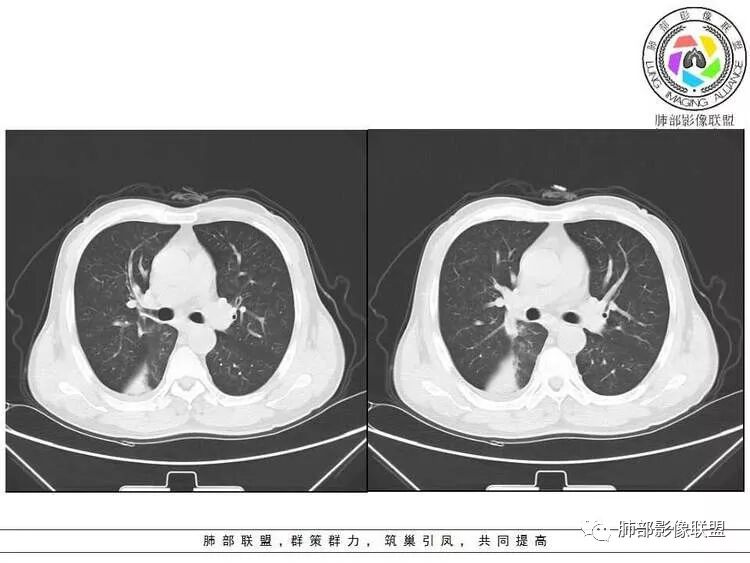

病灶近端支气管通畅,局部体积缩小不明显,外围大内带小,沿支气管树蔓延过来

远端确实有膨隆,边缘凹凸不平,换个角度,这个病灶紧贴着斜裂外带。

南边:紧贴着斜裂过来的一个病灶,它的特点是:外围大,内带小。它整个下叶背段体积与对侧相比稍微缩小一点,但是缩小地不是很厉害。外支朝前下走了,仔细看血管,肺动脉走行自然,直达远端。远端实变区是肉芽肿成分,稍微有一点低密度,没有明显坏死,稍微有一点点坏死。而且附近有很多卫星灶,附近很多斑片影,有一些明显有气道壁增厚,细支气管炎的特点,还有就是下叶其他段很多斑片状影。换个角度,第一如果是肺癌,刚才看到PET-CT提示肺癌伴阻塞性肺炎,这个是不符合的。第二如果是肺癌阻塞性肺炎,近端血管肺动脉走行不会那么自然集聚的,这个是不符合的。理由是:如果这个病灶是肺癌,那么明显属于中央型肺癌,中央型肺癌的特点是近端大,远端小,近端是一个肿块,远端阻塞,远端阻塞是阻塞性炎症或者不张,它应该体积缩小,斑片状实变,不会这么密实。刚才有老师提到支气管,这个片有缺陷的地方,给的图像好像那层,如果把其他图像拿开再重叠一下。

鉴别诊断:肺炎性肺癌,胸膜下起源,外围大,局部占位效应,有膨隆有收缩,这个不太支持。支气管走行里面没有看到支气管进入很自然堵塞的粘液栓的特点。附近这些磨玻璃影,它的磨玻璃影要么边界清楚,要么由内朝外蔓延的,而不是沿着支气管束蔓延的。而且附近斑片状影,有些似乎有结节感,但是大部分不是,它不是我们常见的磨玻璃样结节,有些有,导致像腺泡样结节那种椭圆的沿着血管束分布的,我会把肺炎型肺癌放在待排。

右肺下叶背断肿块,外围大,内带相对狭长         远端有膨隆,边缘模糊、凹凸不平         血管走形自然,病灶近端支气管通畅,沿支气管树蔓延         周边有多发病灶,多为磨玻璃密度且边界不清。